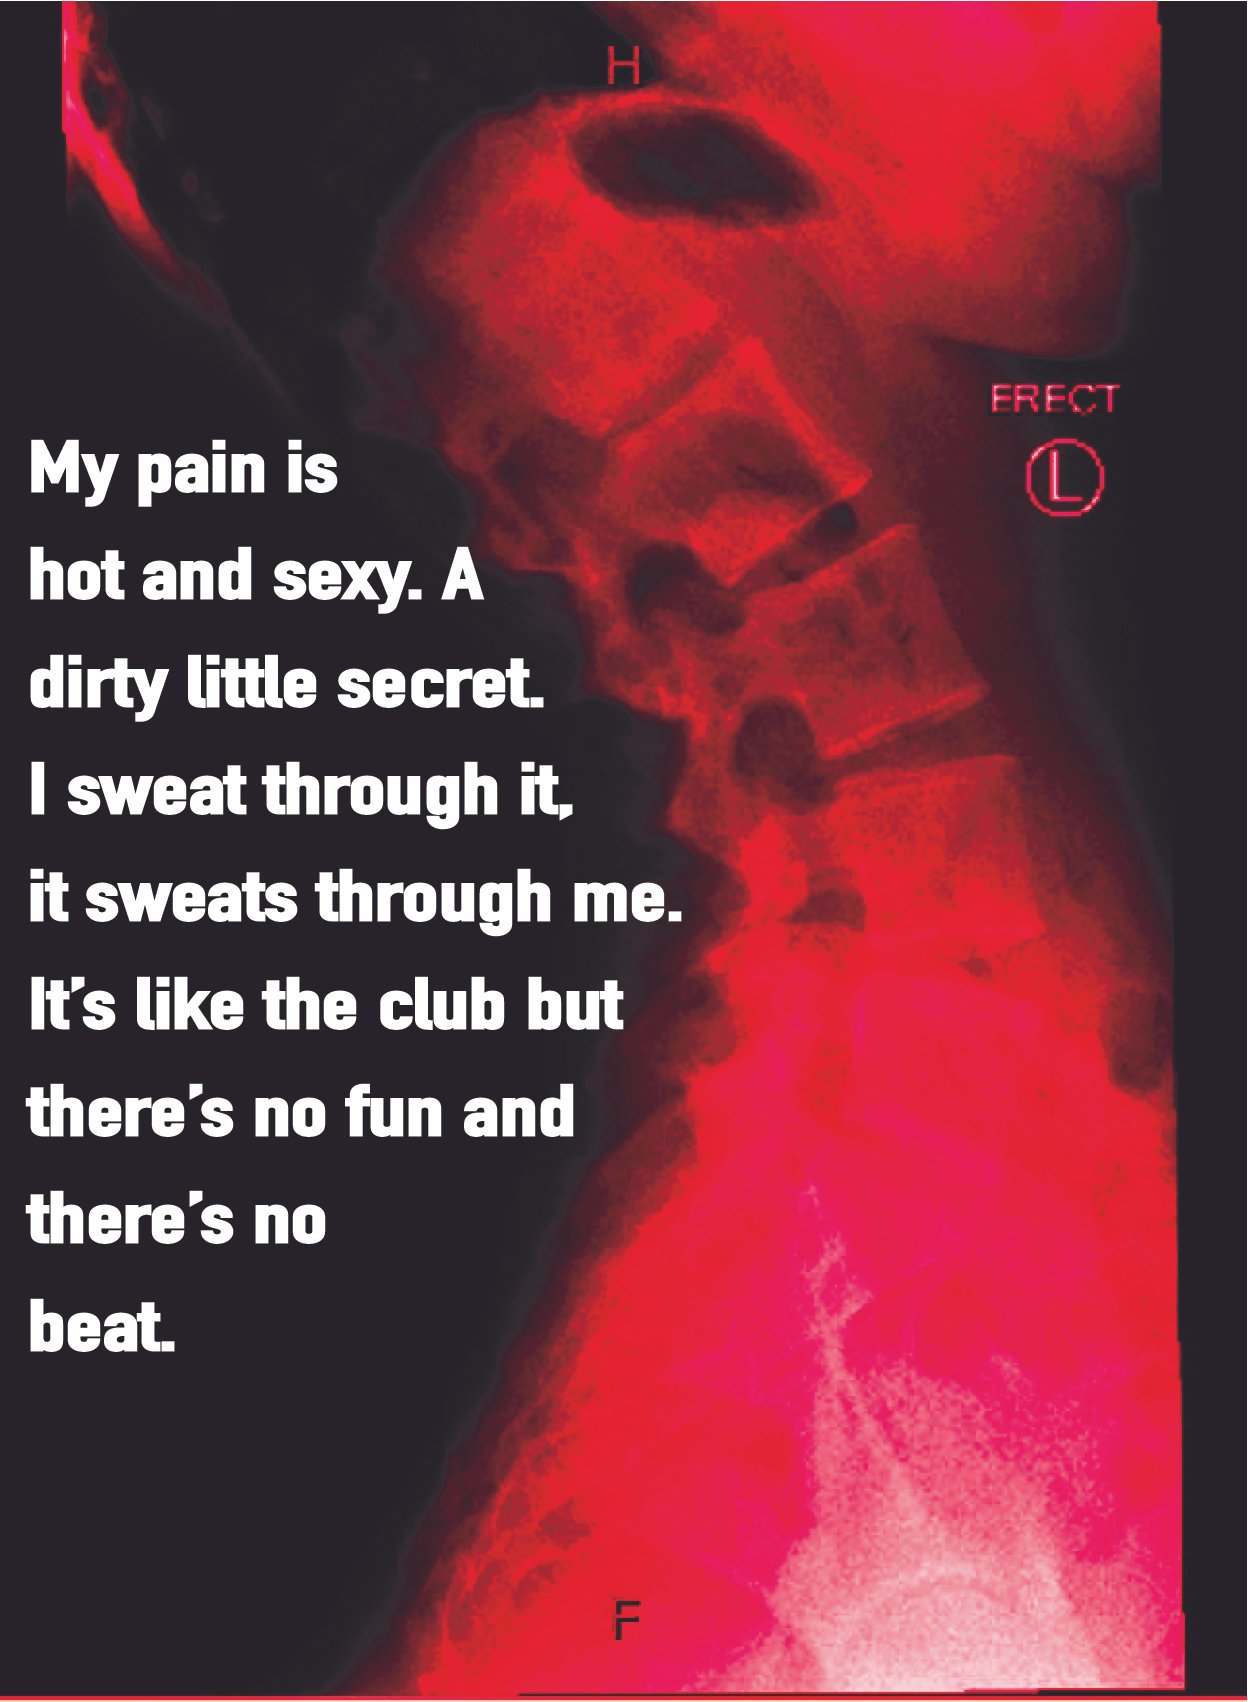

Confessions of a Bad-Backed Young Masc